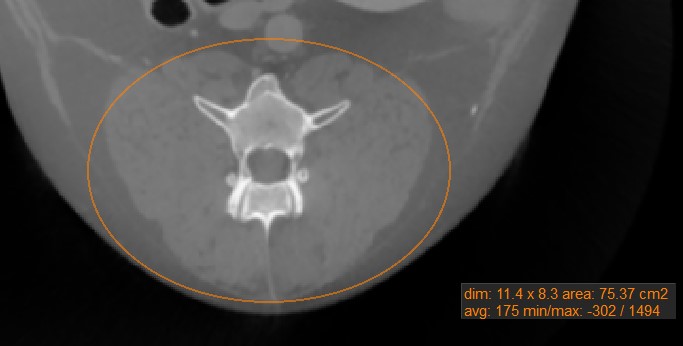

Oval¶

Select the Oval tool and assign it to one of the available mouse buttons. Start the measurement by pressing on the active image slice and drag the mouse to obtain an oval shape. Release the mouse when satisfied

with the size of the marked area.

All available measurement values are displayed alongside the measurement.

Modify the marked area by moving one of the four points describing the rectangle around the oval shape using the Default tool.